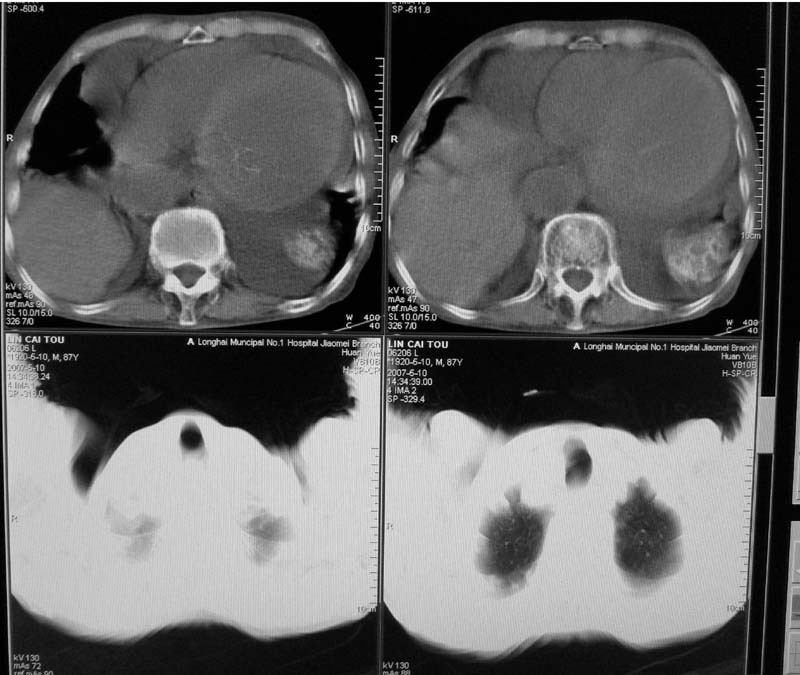

以下是引用小初学者在2007-5-12 16:26:00的发言:[br]1、心衰肺水肿两侧胸腔积液2、心包积液3、心瓣膜钙化